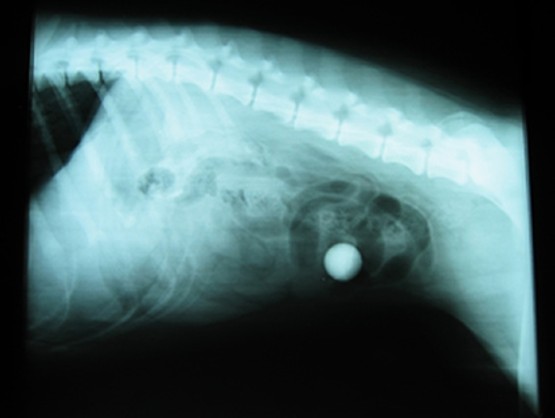

Radiography - foreign body - marble